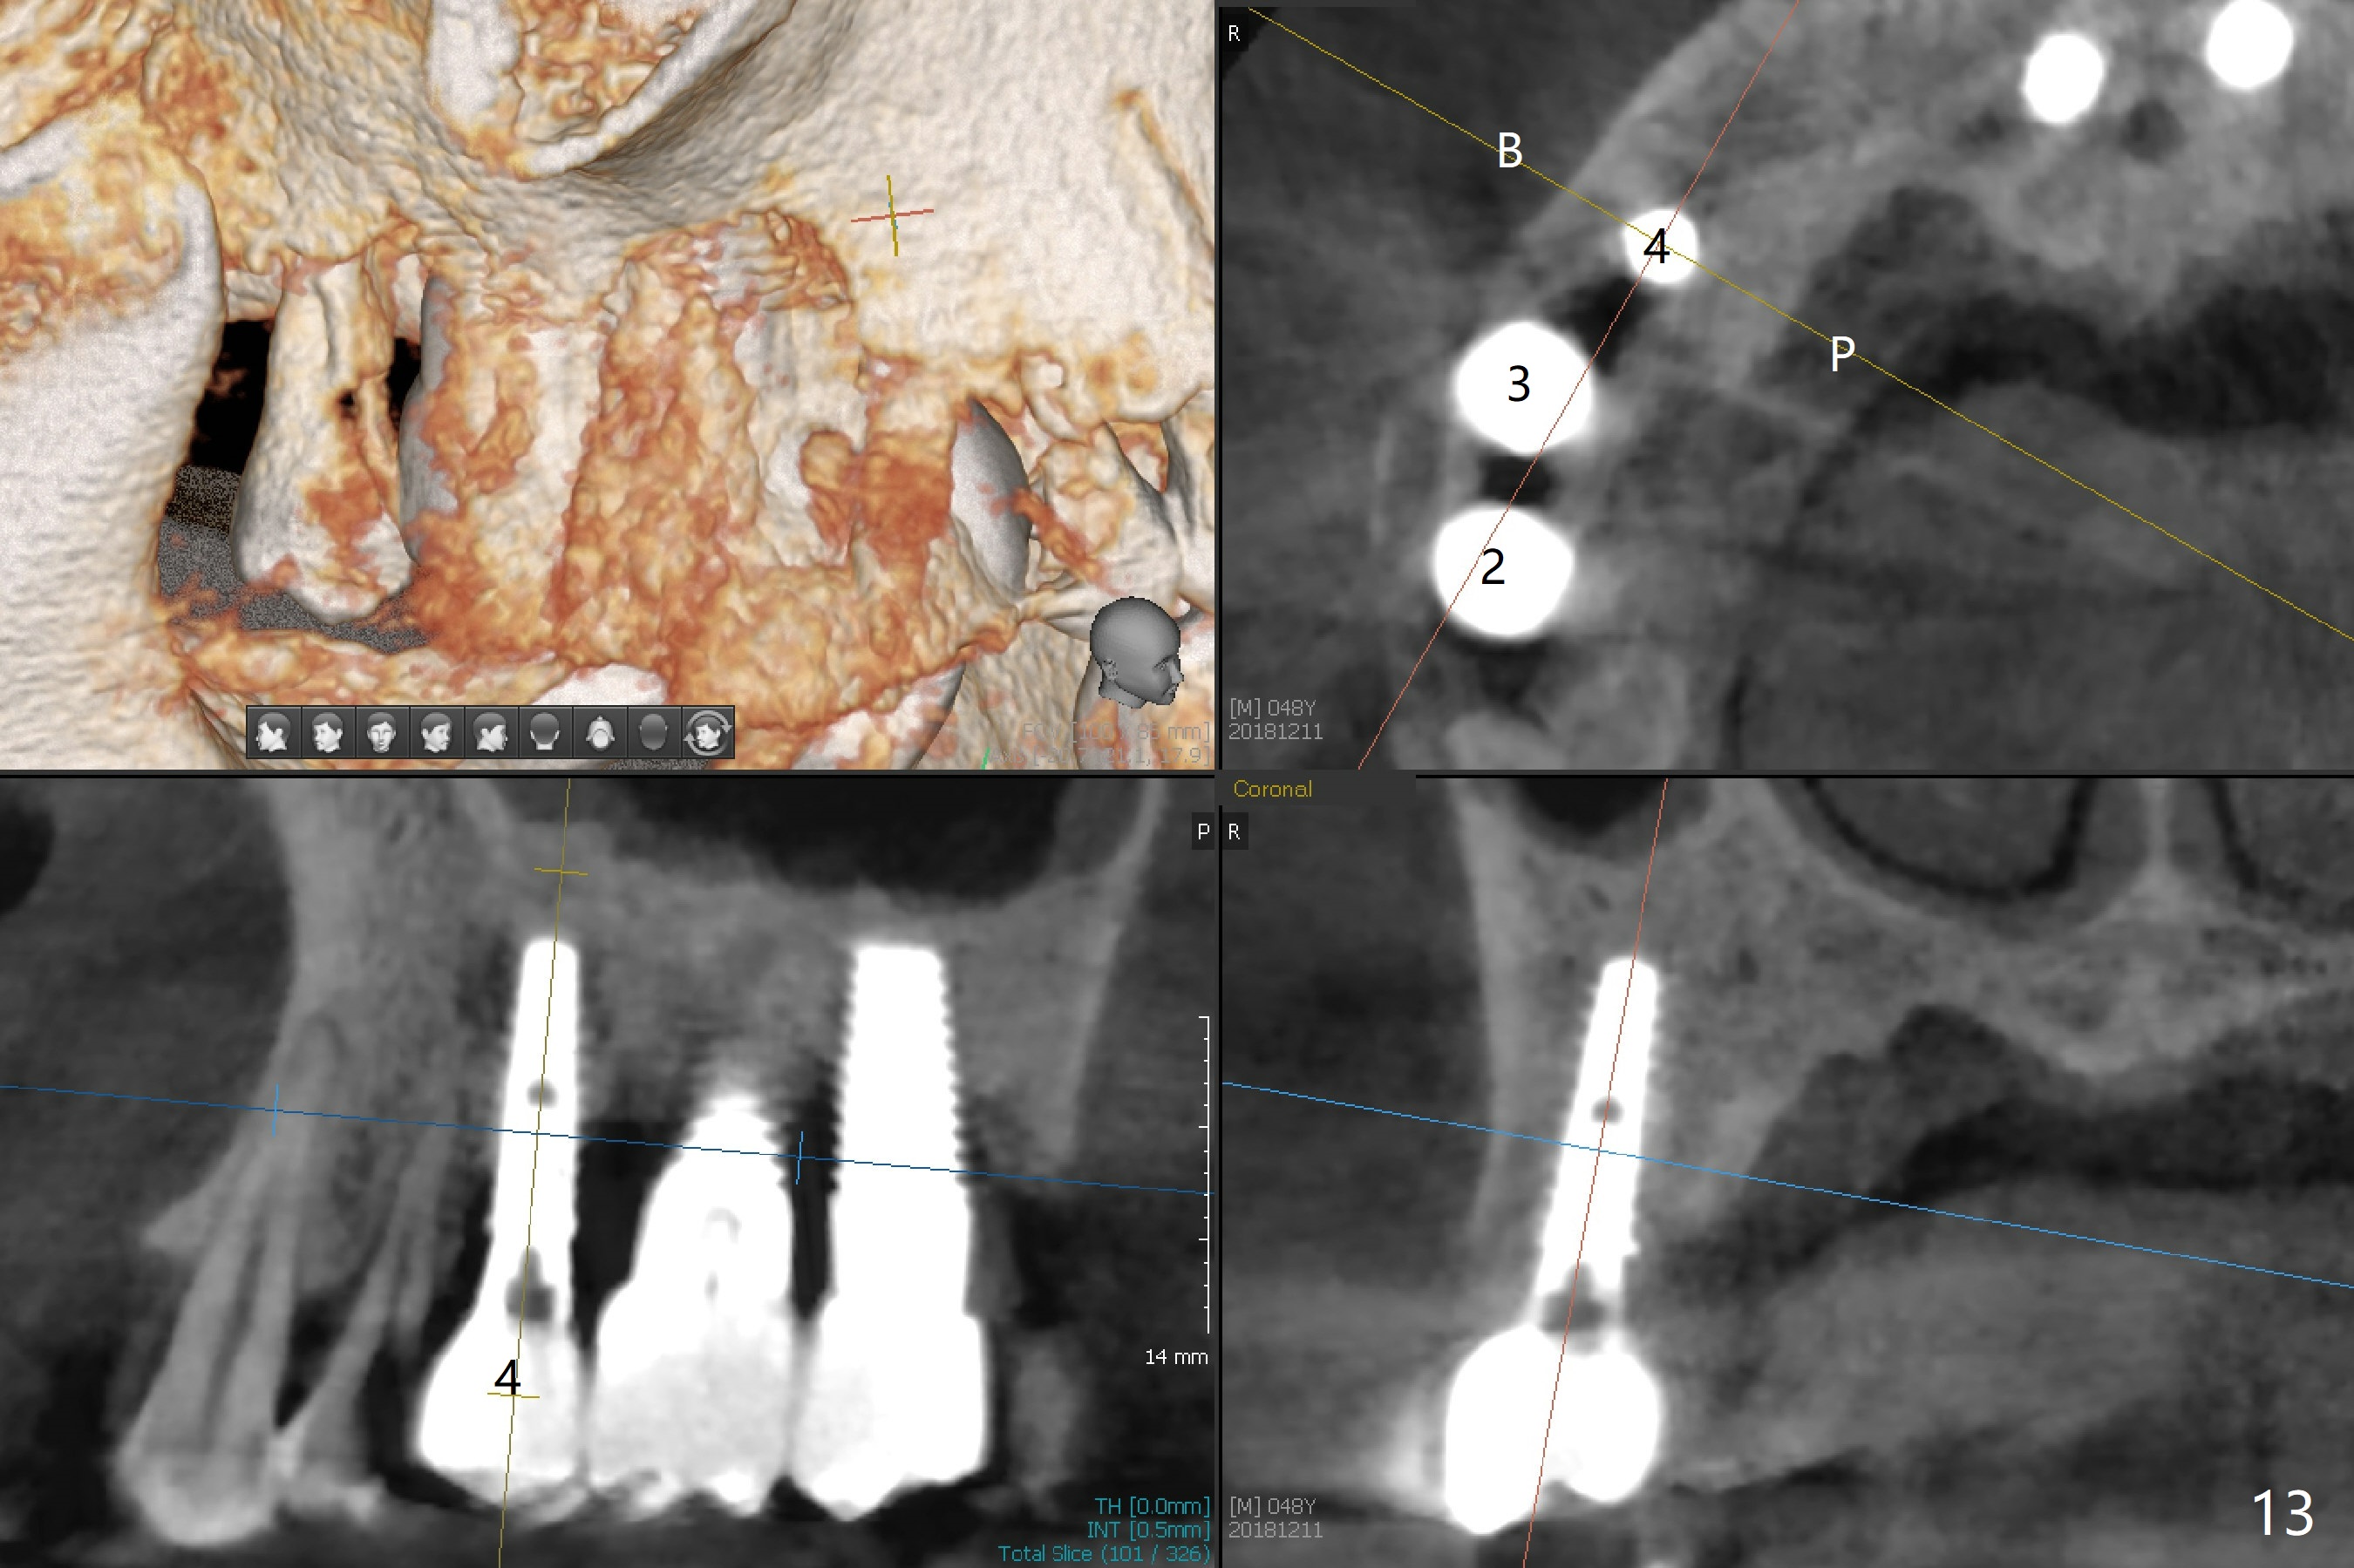

The distal papilla reforms buccally (Fig.8 *) and palatally (Fig.9) 4 months postop. It appears that the 4 mm cuff of the pair abutment (Fig.10 >) is apical to the mesial crest (*). The distal coronal implant threads seem to be covered by bone graft (Fig.11 <). Therefore pair abutments with 5 mm or more cuff are required in cases of the uneven bone. Implants have to be placed deep. CT taken 3 months post cementation (10 months postop) shows that the implant is placed in the middle of the alveolus without apparent thread exposure. CT taken 1 year and 8 months post cementation (Fig.13) shows that the implant is placed in the middle of the alveolus without apparent thread exposure, as compared to those at #2 and 3, which are placed buccal (B).